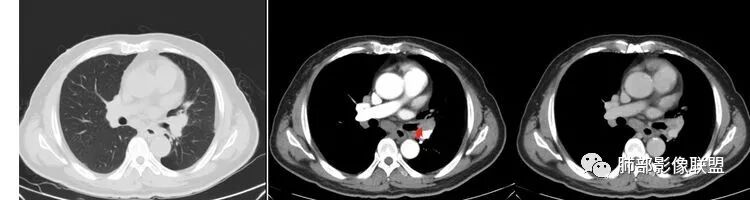

南边:但是我们看纵隔就多发的肿大淋巴结,部分融合成团。

南边:而且这些淋巴结,有些直接主要是压迫支气管壁,但是有些是突入到支气管腔内的。可惜我截的图发不上来。就左上舌段,支气管壁明显的增厚。有些明显腔内突的一个结节的,但是远的没有阻塞的特点。南边:增强以后呢,这个病灶明显强化,部分的似乎有环形强化的迹象,但不是很典型。

我们看这个主支气管的层面,主支气管明显受压,有变形的,但是软骨是没有突破的。

这个区域明显就是一个支气管本身有问题。

但是有一个地方有问题的,左侧的上叶的下舌段这个区域:

左上叶舌段这个气管腔内是有东西凸进去。

首先弥漫性的,支气管壁是一个问题,然后有病灶凸向腔内,那又是一个问题,我有两种想法。

1、支气管壁本身有问题,2周围淋巴结侵犯支气管壁